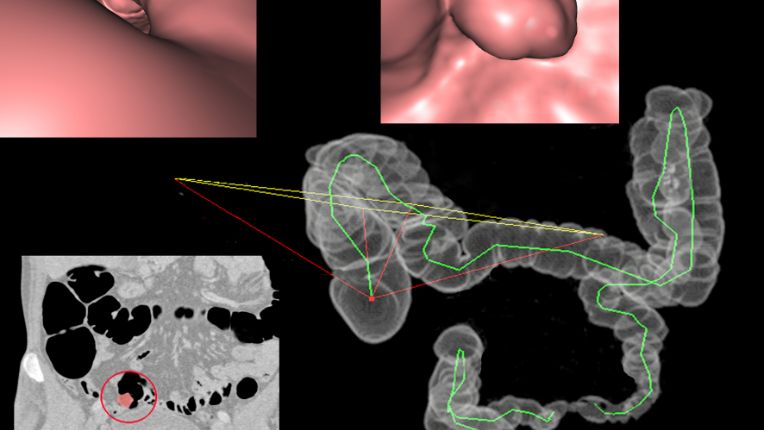

À l'Institut de cancérologie du Hainaut à Valenciennes (59), la chirurgie du côlon assistée par robot permet une prise en charge moins invasive et plus précise.

Aux commandes du robot Da Vinci, le ou la chirurgienne réalise ses gestes comme lors d’une opération classique. Grâce aux manettes, le robot convertit les mouvements du ou de la professionnelle en mouvements précis, en gommant les petits tremblements courants de la main.